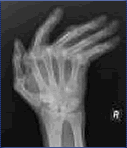

MEDICINA

Lečenje reumatoidnog artritisa

Novi biološki lekovi - nove mogućnosti

Reumatoidni artritis jedan je od najvećih izazova za reumatologiju. Reč je o autoimunskoj bolesti, o hroničnom, stalno napredujućem upalnom propadanju zglobova koje teško remeti svakodnevni život obolelog, uz rizik da će ga za pet do deset godina uvesti u invaliditet. Pad kvaliteta života osobe pogođene ovom teškom bolešću prof. dr Nemanja Damjanov, direktor beogradskog Instituta za reumatologiju i predsednik Udruženja reumatologa Srbije, na nedavnom seminaru o reumatodinom artritisu u Opštoj bolnici Bel Medik, uporedio je sa višedecinijskim tamnovanjem, jer najteži bolesnici vremenom gube radnu sposobnost i bivaju trajno vezani za kuću.